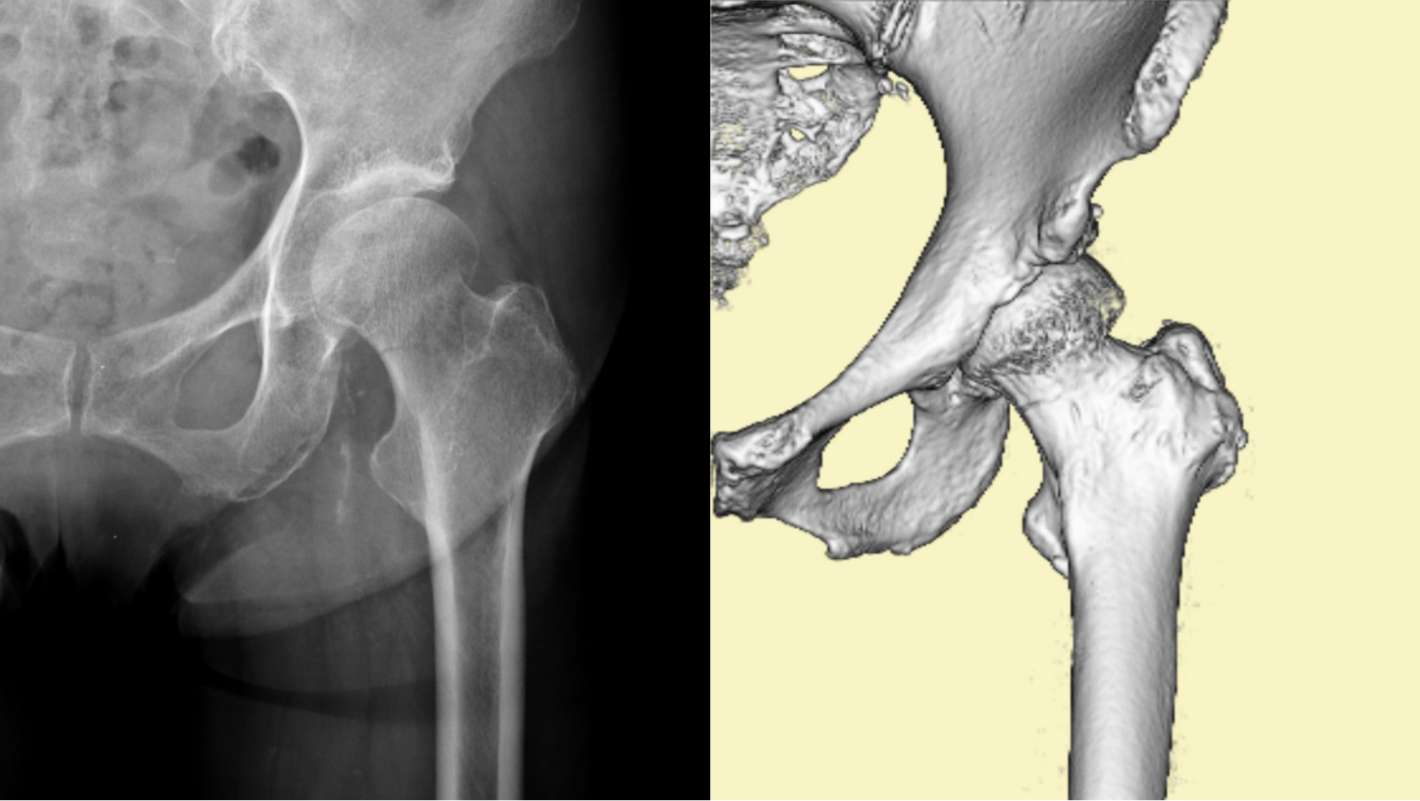

大腿骨骨折の診断

ほとんどの場合、医師はまずX 線検査を行います。さらに詳しい情報が必要な場合は、 CT (コンピューター断層撮影) スキャンを注文することもあります。特定の治療法を推奨する前に、医師はどのような種類の休憩があるかを判断します。最も一般的なタイプは次のとおりです。